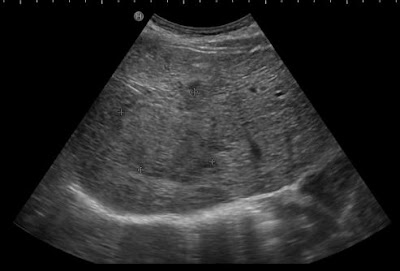

56세 남자 환자이며 만성 B형간염으로 비리어드를 복용하시는 분으로 간암검진으로 초음파를 시행하였는데 간의 우엽에 5cm 이상되는 종양이 발견되었다. 간실질은 간경변은 아니었으며 종양 주변에 저음영의 띠를 두른 듯한 모습이었다. (hypoechoic lim)

간세포암 내지 간담도암이 의심이 되어 바로 Liver dynamic CT 의뢰를 보내었는데 결과는 Cholangiocarcinoma 가 더 근접한 것으로 나왔다.

이분은 초음파를 마지막으로 시행한게 2년 전이었다고 하는데 좀더 자주 초음파를 시행했다면 좀더 초기에 발견할 수 있지 않았을까?